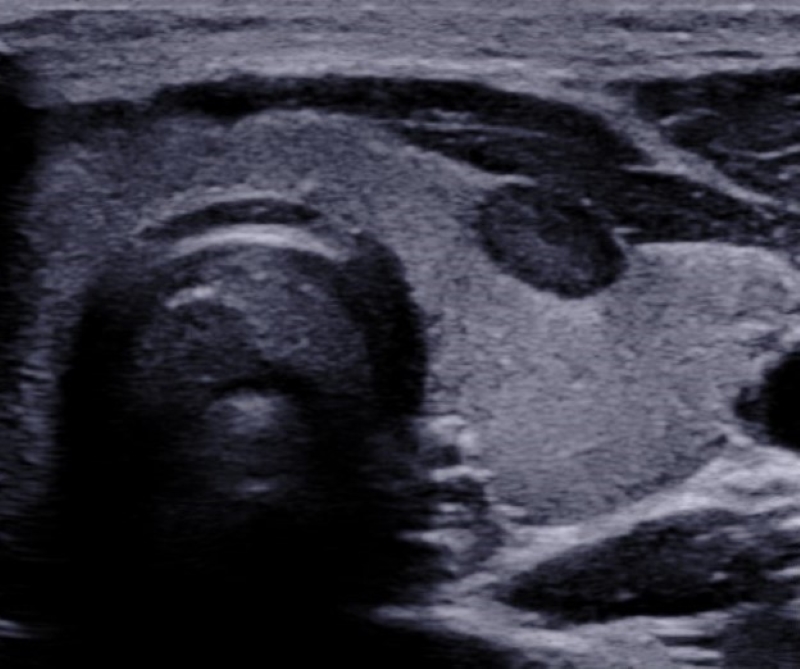

Dureza

La share wave elastography (SWE) es una nueva herramienta ecográfica que mide de manera cuantitativa la dureza o rigidez de un tejido, y reduce la subjetividad del diagnóstico clínico de la elasticidad de los nódulos. La SWE es efectiva para aumentar la sensibilidad de la ecografía en la detección de neoplasias tiroideas. Algunos autores definen al aumento de la elasticidad de un nódulo en relación con el parénquima tiroideo adyacente como mayor riesgo de malignidad. Hazem et al. establecen un valor medio para nódulos benignos de 33,46 ± 5,02 kPa y de 49,71 ± 11,16 kPa para nódulos malignos11,25. Las guías y recomendaciones de SWE publicadas por Ferraioli et al. en 2021 sugieren que los nódulos benignos muestran una elasticidad media de 15,3-28 kPa y que el punto de corte óptimo entre nódulos benignos y malignos es de 34,5-37,5 kPa26) (Figs. 21 y 22).